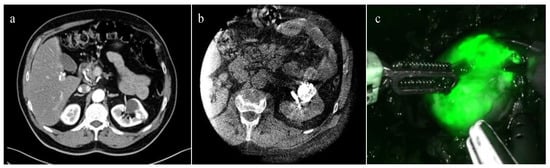

- Simone, G.; Tuderti, G.; Anceschi, U.; Ferriero, M.; Costantini, M.; Minisola, F.; Vallati, G.; Pizzi, G.; Guaglianone, S.; Misuraca, L.; et al. “Ride the Green Light”: Indocyanine Green–marked Off-clamp Robotic Partial Nephrectomy for Totally Endophytic Renal Masses. Eur. Urol. 2019, 75, 1008–1014. [Google Scholar] [CrossRef] [PubMed]

- Tuderti, G.; Brassetti, A.; Mastroianni, R.; Misuraca, L.; Bove, A.; Anceschi, U.; Ferriero, M.; Guaglianone, S.; Gallucci, M.; Simone, G. Expanding the limits of nephron-sparing surgery: Surgical technique and mid-term outcomes of purely off-clamp robotic partial nephrectomy for totally endophytic renal tumors. Int. J. Urol. 2022, 29, 282–288. [Google Scholar] [CrossRef] [PubMed]

- Nardis, P.G.; Cipollari, S.; Lucatelli, P.; Basilico, F.; Rocco, B.; Corona, M.; Cannavale, A.; Leonardo, C.; Flammia, R.S.; Proietti, F.; et al. Cone-Beam CT-Guided Transarterial Tagging of Endophytic Renal Tumors with Indocyanine Green for Robot-Assisted Partial Nephrectomy. J. Vasc. Interv. Radiol. 2022, 33, 934–941. [Google Scholar] [CrossRef] [PubMed]